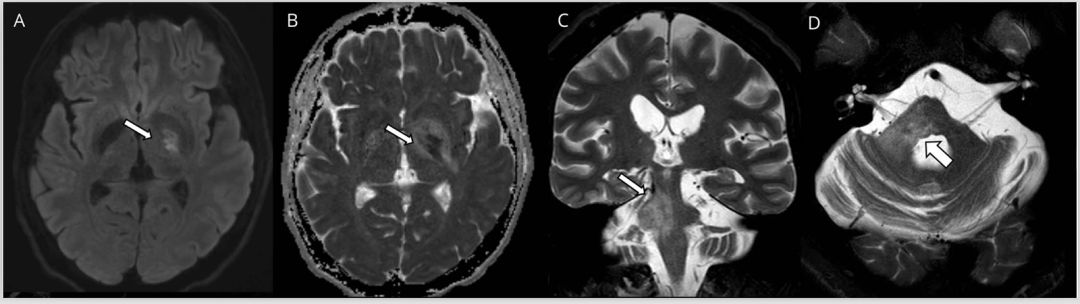

多发性硬化(MS)是中枢神经系统的获得性炎性脱髓鞘疾病,在MRI上病灶通常为卵圆形且界限清晰,T2和FLAIR序列呈高信号改变(图1)。在慢性病变过程中当轴突受损时,T1序列上可见低信号的黑洞征,但急性期也可能见到。新发病灶在3天到3个月内(平均3周)可见强化。虽然MS病灶会出现弥散受限,但当弥散发生变化时,弥散率通常会增加。当存在弥散受限时,特别是多发病灶和不在典型部位时,应考虑其他病因,例如SS或血管炎。

MS的病灶通常发生在脑室周围、胼胝体周围、深部白质、皮层和近皮层部位、脑干、小脑以及视神经和脊髓。在T2 *序列上的中心静脉征有助于MS病变与其他炎性和非炎性疾病(包括NMOSD)的鉴别,超过80%的MS病变位于静脉周围。而相比之下,NMOSD为32%,CNS血管病变为14%。

MS病灶通常位于脑干的外围,如脑桥前部或三叉神经进入区,或位于导水管周围灰质的腹侧,而慢性小血管疾病会影响穿支动脉的区域(例如脑桥中央),并常伴有其他血管病变(腔隙性梗塞或微出血)。

图1多发性硬化症患者的MRI影像。轴位T2加权(A,B)显示脑桥外围界限清楚的卵圆形病灶(箭头)。矢状位FLAIR图像(C,D)显示胼胝体下表面的病灶(C)和垂直于胼胝体的病灶(Dawson指征)(D)。